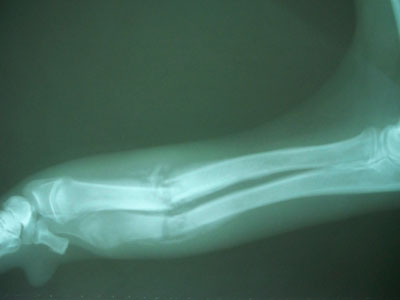

Τσοπανόσκυλο 7 μηνών με 2 εβδομάδων τέλειο κάταγμα κάτω τρίτου μεσότητας διάφυσης αριστερής κερκίδας και ωλένης. (από φιλοζωικό Πέραμα)